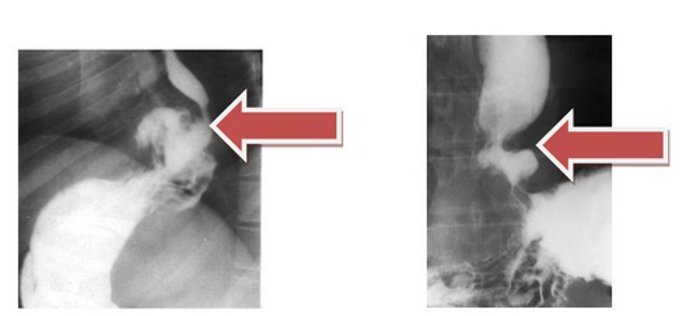

- Рентгенологическое исследование грудной и брюшной полостей. Перед процедурой следует воздержаться от пищи в течение 6 часов, а за 10–20 минут до исследования необходимо выпить бариевую суспензию, которую предоставляют перед кабинетом рентгенографии. Этот метод позволяет в реальном времени наблюдать за движением бария через пищевод в желудок.